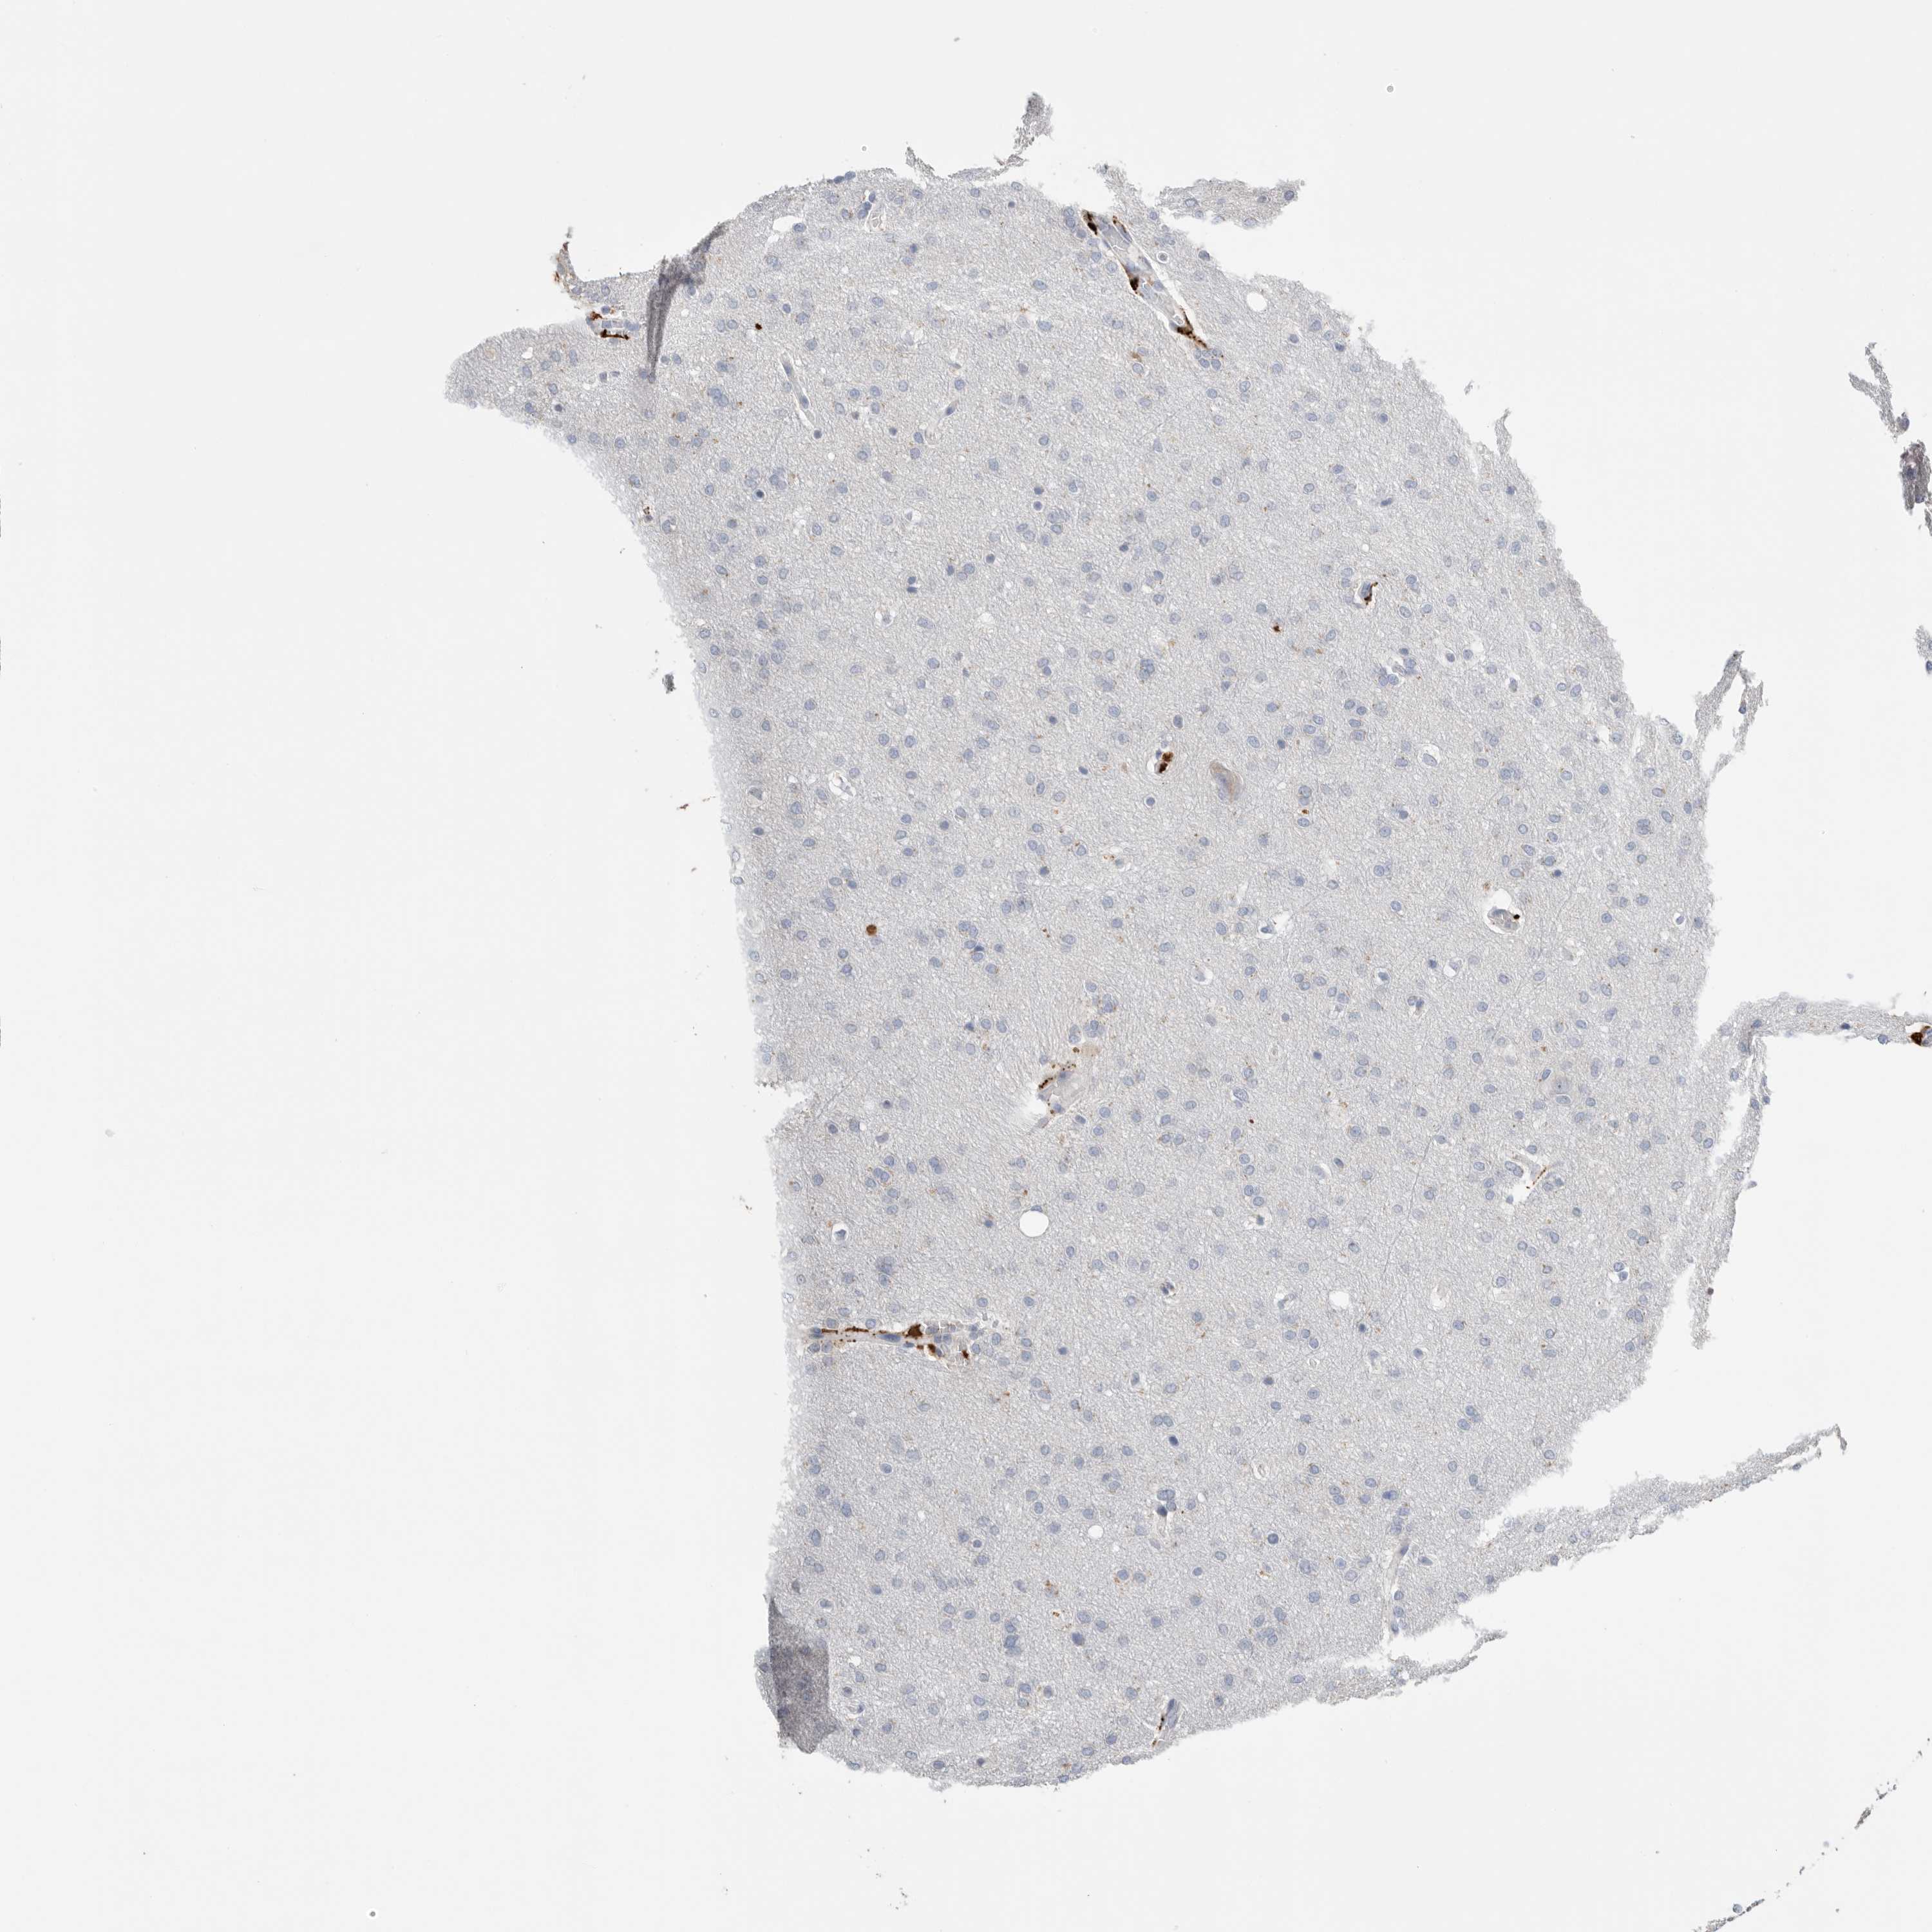

GLIOMA - Protein expressioni

A mouse-over function shows sample information and annotation data. Click on an image to view it in a full screen mode. Samples can be filtered based on level of antibody staining by selecting one or several of the following categories: high, medium, low and not detected. The assay and annotation is described here.

Note that samples used for immunohistochemistry by the Human Protein Atlas do not correspond to samples in the TCGA dataset.

Antibody stainingi

Antibody staining in the annotated cell types in the current human tissue is reported as not detected, low, medium, or high, based on conventional immunohistochemistry profiling in selected tissues. This score is based on the combination of the staining intensity and fraction of stained cells.

Each image is clickable and will lead to virtual microscopy that enables deeper exploration of all samples and also displays staining intensity scores, fraction scores and subcellular localization as well as patient and tissue information for each sample.

Antibody HPA025226

Antibody CAB019296

Staining

High

Medium

Low

Not detected

Intensity

Strong

Moderate

Weak

Negative

Quantity

>75%

75%-25%

<25%

None

Location

Nuclear

Cytoplasmic/membranous

Cytoplasmic/membranous,nuclear

Glioma, malignant, High grade

Glioma, malignant, Low grade